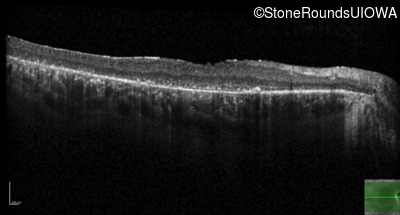

Optical Coherence Tomography - Right - 20/125 -2

Exemplar / OCT Stack

OCT Stack